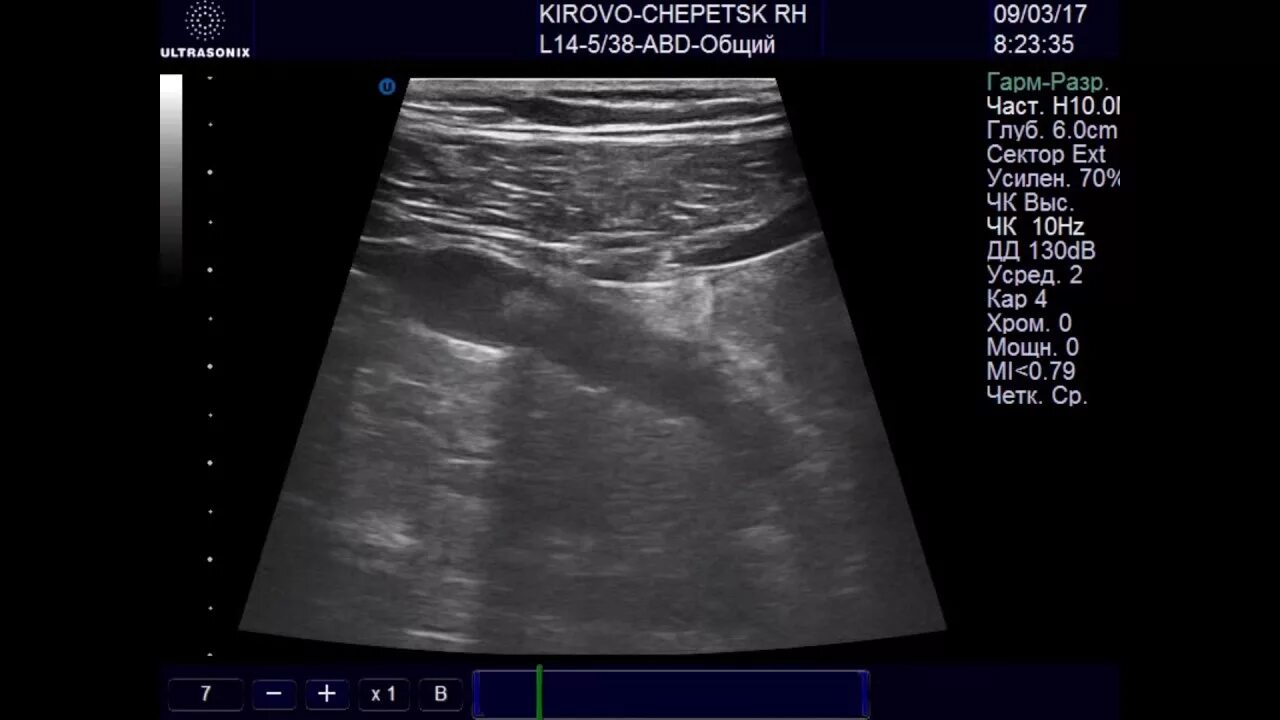

Аппендицит на узи можно ли